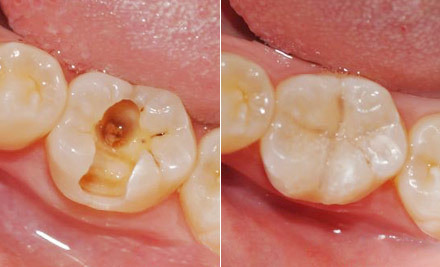

补牙为什么越早越好 如果患了龋病就应尽可能地早修补,因为龋洞经过修补后可以阻止龋病病变的发展,及早恢复牙齿的功能,保持牙列的完整若不进行及时治疗,病变就会越来越大,从浅龋发展到深龋... 补牙 范姜英杰 569 2023-11-25

什么是龋齿 龋齿,俗称“虫牙”、“蛀牙”,它并不是虫子把牙齿蛀坏了,而是在以细菌为主的多种因素影响下,牙齿的牙釉质、牙本质或牙骨质发生的一种慢性、进行性、破坏性的疾病。龋齿... 补牙 吴芳芳 550 2023-11-15